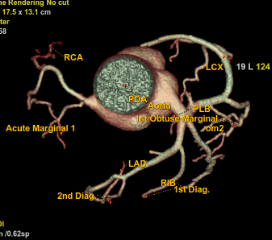

Coronary Angiogram

A CT Coronary Angiogram is a non-invasive imaging test that uses a CT scanner, and contrast dye to create detailed 3D pictures of your heart's arteries, revealing plaque, blockages, or narrowing (stenosis) that can cause heart problems like chest pain.

3D Vessel Analysis

CORONARY ASSESSMENT

- •Non-invasive coronary artery evaluation

- •Stenosis and blockage detection

- •Calcium scoring for risk assessment

- •3D cardiac reconstruction